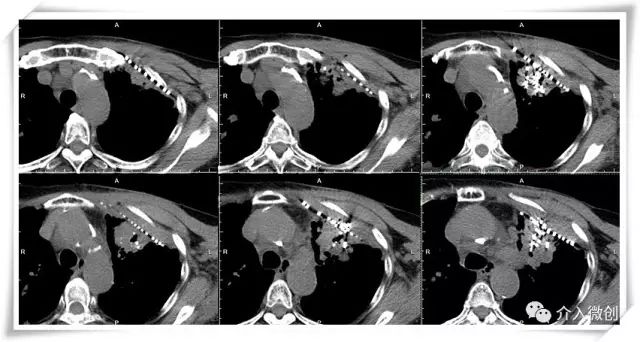

CT示左侧胸壁肿瘤转移

CT示左肺门肿瘤转移,侵犯、压迫左上肺支气管,累及左肺动脉

CT引导下放射性粒子植入左侧胸壁病灶及左肺肺门病灶